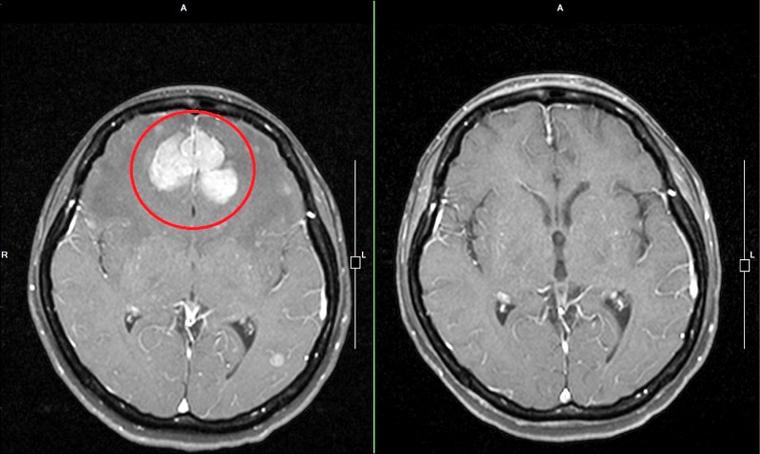

核心问题:肺腺癌、脑转移、脑梗,这三者是什么关系?

这三者同时出现,绝不是孤立的事件,它们之间存在着密切且复杂的联系。

- 脑转移:是癌细胞从肺部通过血液循环“跑”到了大脑,并形成了新的肿瘤,这是癌症的晚期表现之一。

- 脑梗(缺血性脑卒中):是大脑的血管被堵塞了,导致脑组织缺血坏死。

关键点在于:脑梗的发生,很可能与肺腺癌和脑转移有直接关系,而不仅仅是“巧合”。

- 头颅MRI + DWI序列:这是诊断早期脑梗的“金标准”,可以清晰地显示缺血坏死的脑组织。